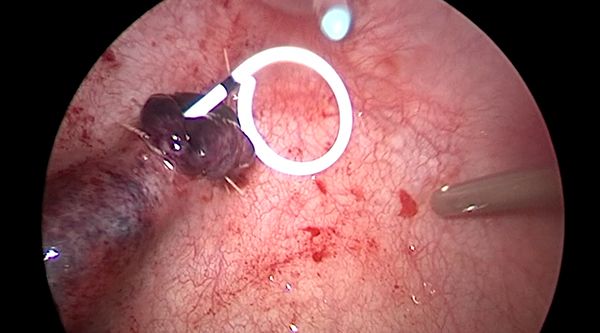

一名14岁男性青少年因活动后血尿检查发现右肾积水并右肾结石,进一步检查发现患儿右肾积水的原因是肾盂输尿管连接部梗阻所致。由于患儿肾盂输尿管连接部狭窄,常规输尿管软镜碎石无法实施。由于结石位于右肾下盏,盏颈狭窄、腹腔镜下无法直接取石。经小儿泌尿外科讨论后,决定在患儿行腹腔镜肾盂成形术的同时联合输尿管软镜进行右肾下盏激光碎石。手术在吴荣德教授指导下,由刘伟主任医师、杜国强副主任医师等共同完成。经腹腔镜探查发现患儿肾盂输尿管连接部狭窄,狭窄段长0.5cm,肾盂扩张积水。于肾盂切开约0.5cm,自腹壁置入输尿管软镜经肾盂切口进入,在下盏内见一大小约1.0×0.8cm黄褐色桑葚样结石,经输尿管软镜置入钬激光光纤予以碎石。碎石后取出大块结石颗粒,吸净碎屑后行腹腔镜下右肾盂成形术。患儿术后恢复良好,顺利出院。后期患儿规律复查,未再出现血尿、腹痛等不适症状。

一名8岁女性儿童因血尿检查发现左肾输尿管积水并左输尿管末端结石入院治疗,检查发现患儿为输尿管末端狭窄合并左肾结石。由于患儿输尿管末端狭窄可经气膀胱腹腔镜手术,无法处理左肾结石,并且输尿管末端狭窄无法行输尿管软镜手术。经全科讨论后,决定在患儿行气膀胱腹腔镜输尿管再植的同时联合输尿管软镜进行左肾激光碎石。手术在吴荣德教授指导下,由刘伟主任医师、杜国强副主任医师等共同完成。气膀胱腹腔镜下切除左侧输尿管末端狭窄,经尿道置入输尿管软镜经输尿管末端进入,在下盏内见一大小约0.8×0.7cm黄褐色扁圆形结石,经输尿管软镜置入钬激光光纤予以碎石。碎石后行左侧输尿管膀胱再植术(Leadbetter术式)。患儿术后恢复良好,顺利出院。后期患儿规律复查,未再出现血尿、腹痛等不适症状。